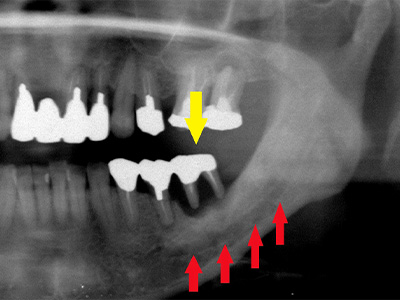

40代女性。上顎前歯を抜歯、虫歯と歯槽膿漏の状態が悪く、抜歯されたのですが、歯を支える歯槽骨が大きく吸収されてしまっていました(黄色矢印)。

インプラント治療を希望されていたのですが、下顎骨の中を通る神経(赤色矢印)が近接していて、骨が不足しているためインプラントの埋入が困難な状況でした。 -